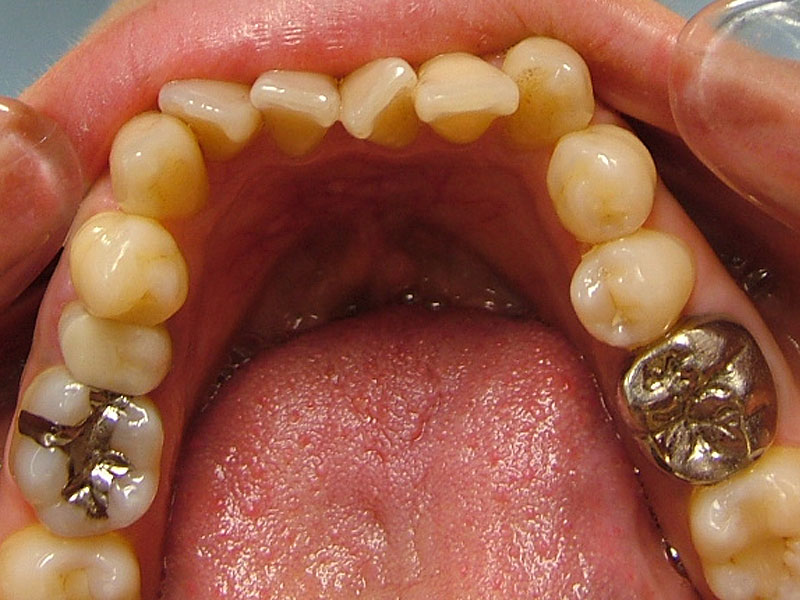

術前

• 初診:2006年、2014年―矯正治療を含めた一口腔単位の治療開始、治療当時、30代女性、非喫煙者

• 主訴:できれば歯並びを良くし歯を白くしたい。

• 治療方針:親知らず3本抜歯、上下小臼歯4本抜歯、矯正用インプラント使用のワイヤー矯正、修復処置、保定(上マウスピース、下ワイヤー)、メンテナンス